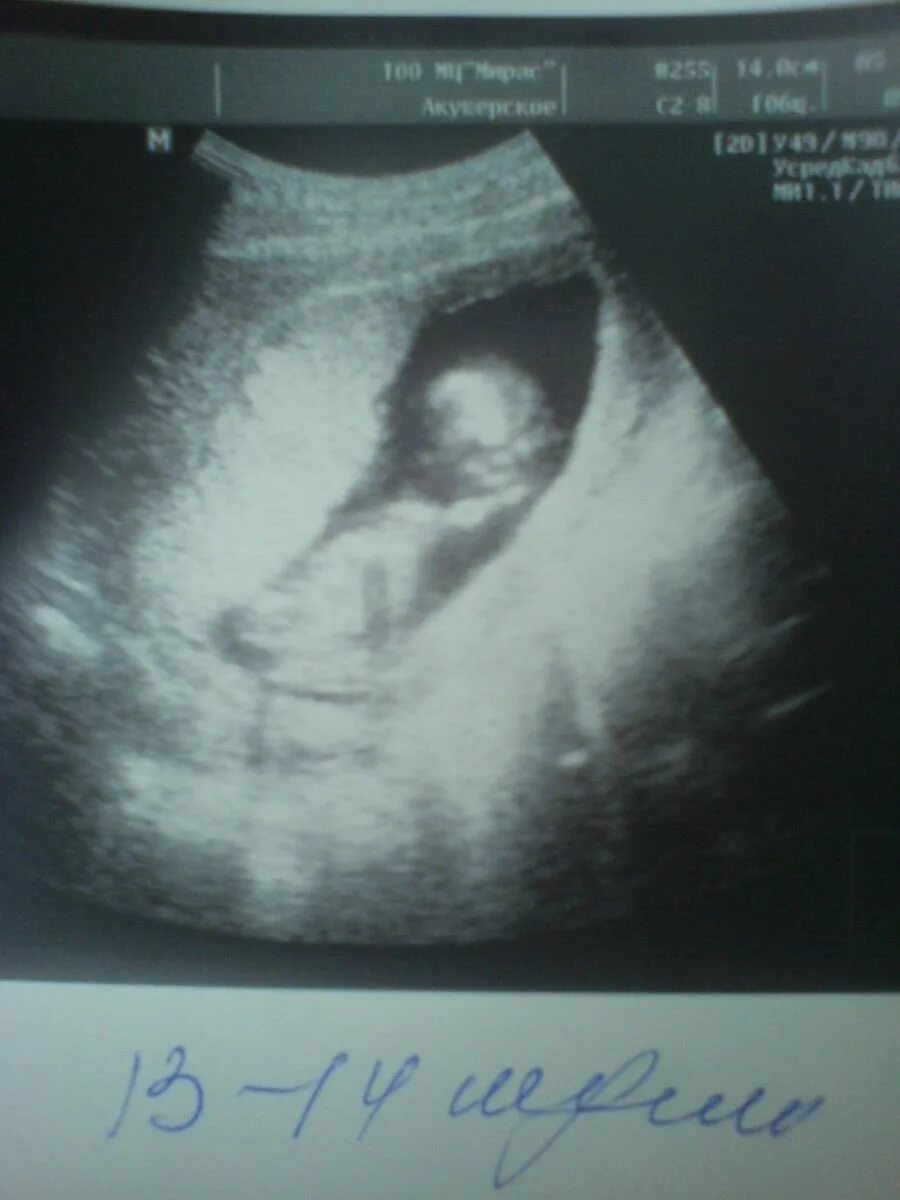

13 недель как выглядит малыш